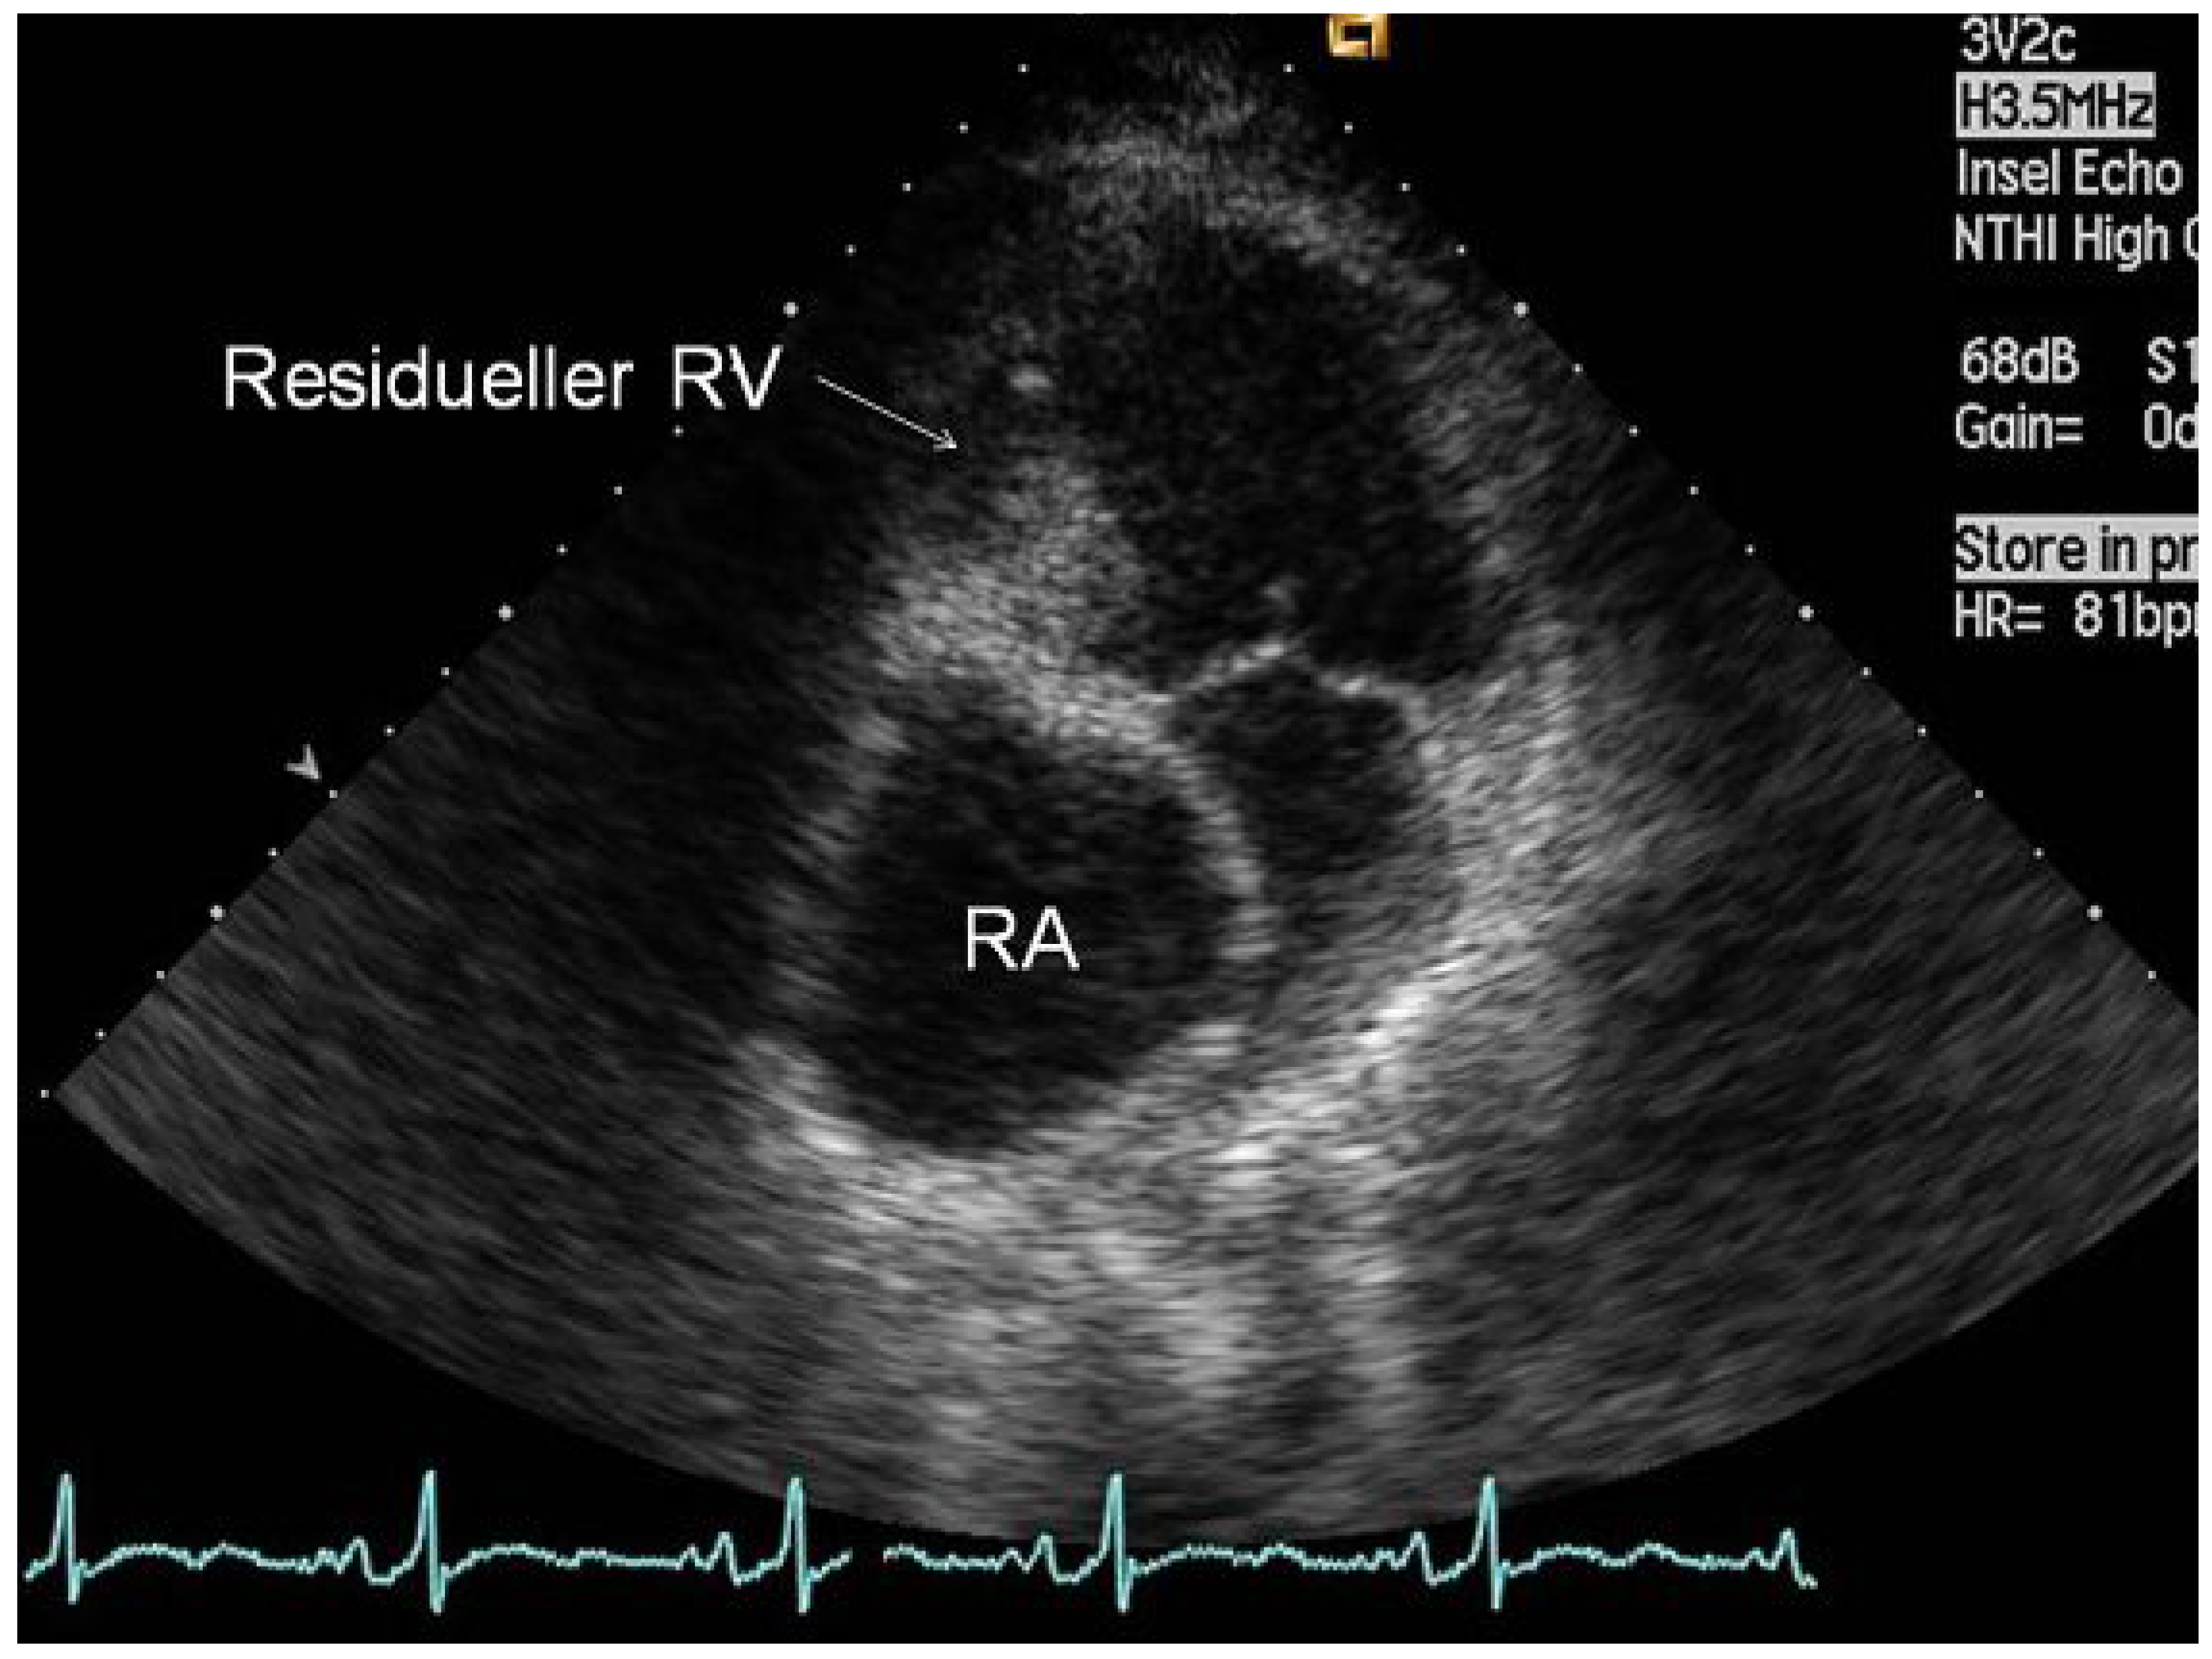

Abbildung 2.

Präoperative transthorakale Echokardiographie in der apikalen «4-Kammer»-Ansicht mit Darstellung des massiv dilatierten rechten Vorhofes (RA) und Vorwölbung des atrialen Septums. Sichtbar sind auch die Gewebebrücke anstelle der Trikuspidalklappe sowie der residuelle «rechte Ventrikel» (RV).

Abbildung 2.

Präoperative transthorakale Echokardiographie in der apikalen «4-Kammer»-Ansicht mit Darstellung des massiv dilatierten rechten Vorhofes (RA) und Vorwölbung des atrialen Septums. Sichtbar sind auch die Gewebebrücke anstelle der Trikuspidalklappe sowie der residuelle «rechte Ventrikel» (RV).

Die Patientin wurde 1984 mit einer Trikuspidalatresie und einem grossen Ventrikelseptumdefekt, einer Transposition der grossen Arterien und einer subvalvulären Pulmonalstenose geboren. In den ersten Lebensjahren bestand eine «balancierte» Physiologie. Die Pulmonalstenose verhinderte die Entwicklung einer pulmonalen Hypertonie. 1992 wurde bei ihr als erste Patientin am Inselspital eine Fontan-Zirkulation angelegt, in der das rechte Vorhofohr mit dem Truncus pulmonalis verbunden wurde (atriopulmonale Anastomose; Abb. 1B). Während der nachfolgenden Jugendzeit war sie körperlich gut belastbar und beschwerdefrei. In den letzten drei Jahren beklagte sie zunehmend rezidivierende, mehrmals täglich auftretende, symptomatische Tachykardien von mehreren Minuten Dauer, die sie im Alltag einschränkten. Als weiteres bestand eine progrediente Leistungsintoleranz, die sich in der Spiroergometrie mit einer Maximalbelastung von 90 Watt und VO2max von 21.3 mL/min/kg (58% des Solls) ausdrückte. Klinisch bestand eine leichte Hypoxämie mit einem Biox von 90%. Echokardiographisch zeigten sich eine normale Funktion des linken Ventrikels und der Klappen sowie ein eindrücklich dilatierter rechter Vorhof (Abb. 2). Durch die Vorhofsdilatation kam es zu einer retrokardialen Kompression der rechtsseitigen Lungenvenen (Abb. 3).